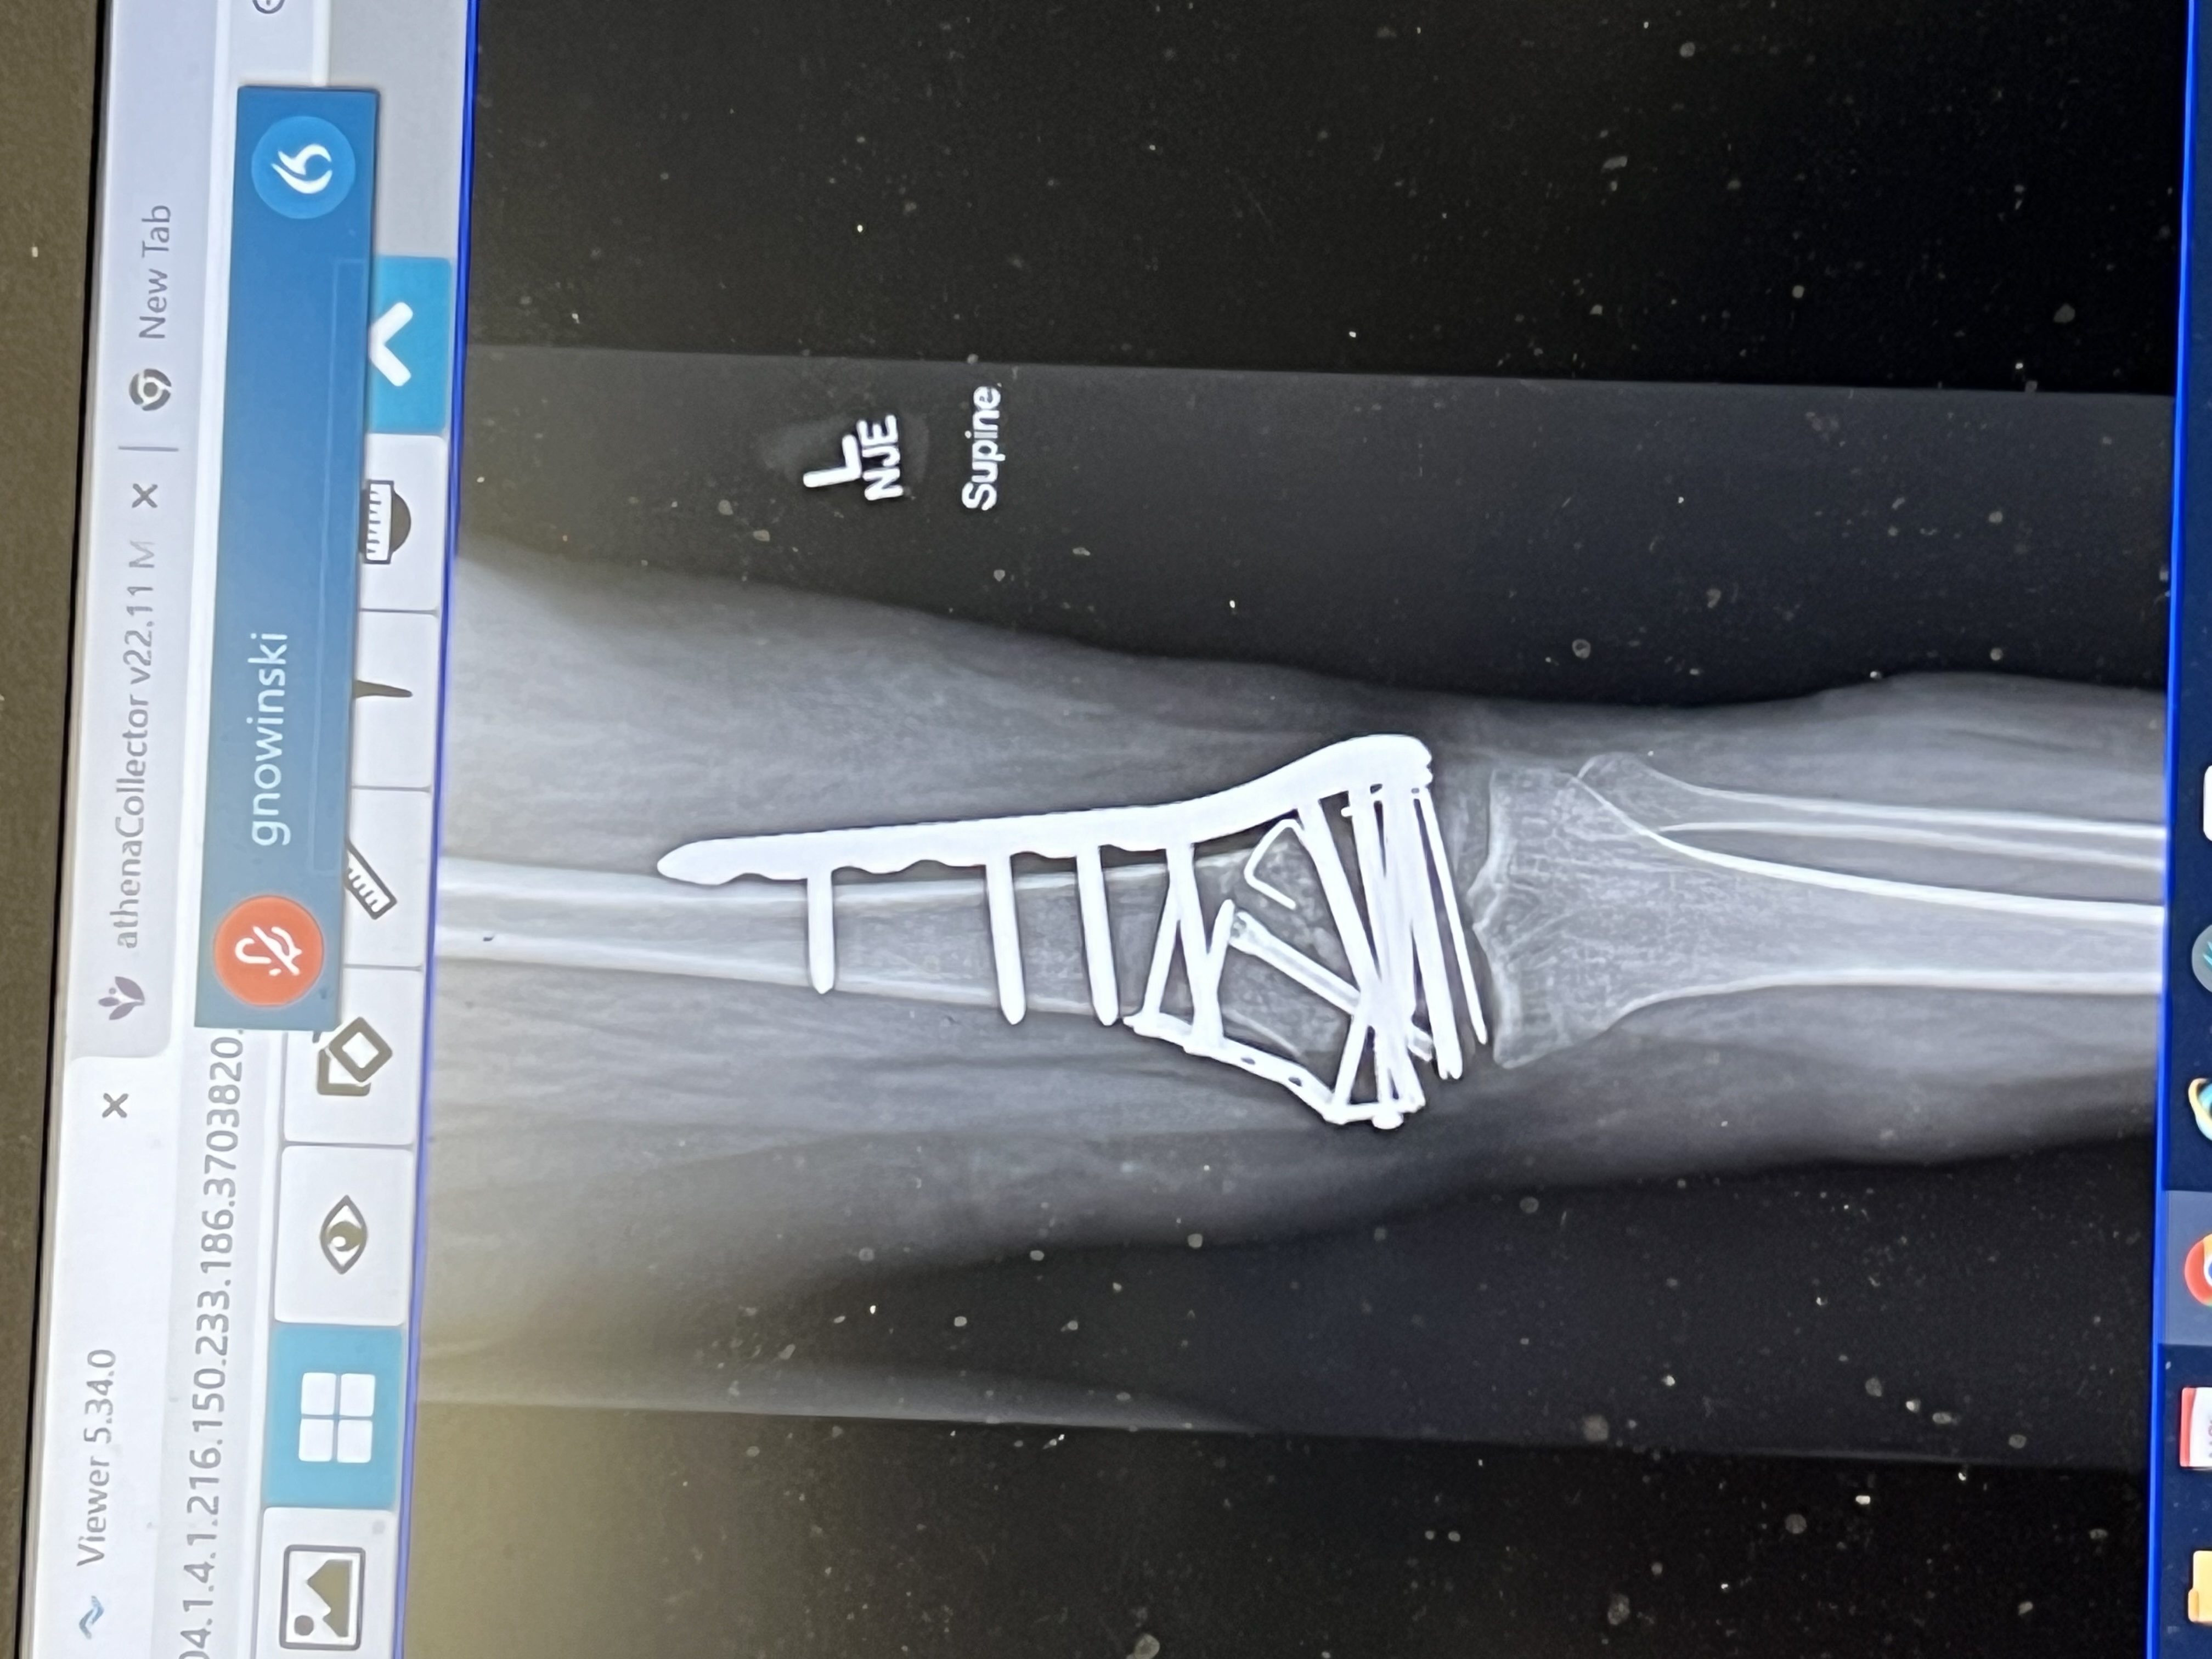

Koneley fell on October 17, 2022. She just returned home on November 8, 2022. During that time, she was in an urgent care and then transferred to two emergency rooms after xrays determined she needed advanced care. She had a 5 hour surgery on October 18, 2022. We spent a week on an orthopedic floor and then 2 more weeks to on a rehabilitation floor. She is home now. She is unable to bare weight or bend her leg. She broke her femur in 3 places, tibia and knee. It is being held together by numerous screws, nails, and a plate. She has a wheelchair and will be immobilized at least anther 4 weeks and it could take up to 2 months before she walks again. The bills are starting to come in and not everything is covered by insurance. She will need ongoing Physical and Occupational Therapy at each phase of her recovery. Our goal is to get her back to as close as she was before the accident. Most of you know, Koneley was born with Cebral Palsy that affected her mentally and physically. She has additional physical problems as well. This just compounded her medical conditions and expenses. We are so proud of her. She just wants to walk and go back to school. Whether you send a good thought, prayer or help out in some other way, know you have a special place in all of our hearts. Thanks in advance for your thoughtfulness and kindness.